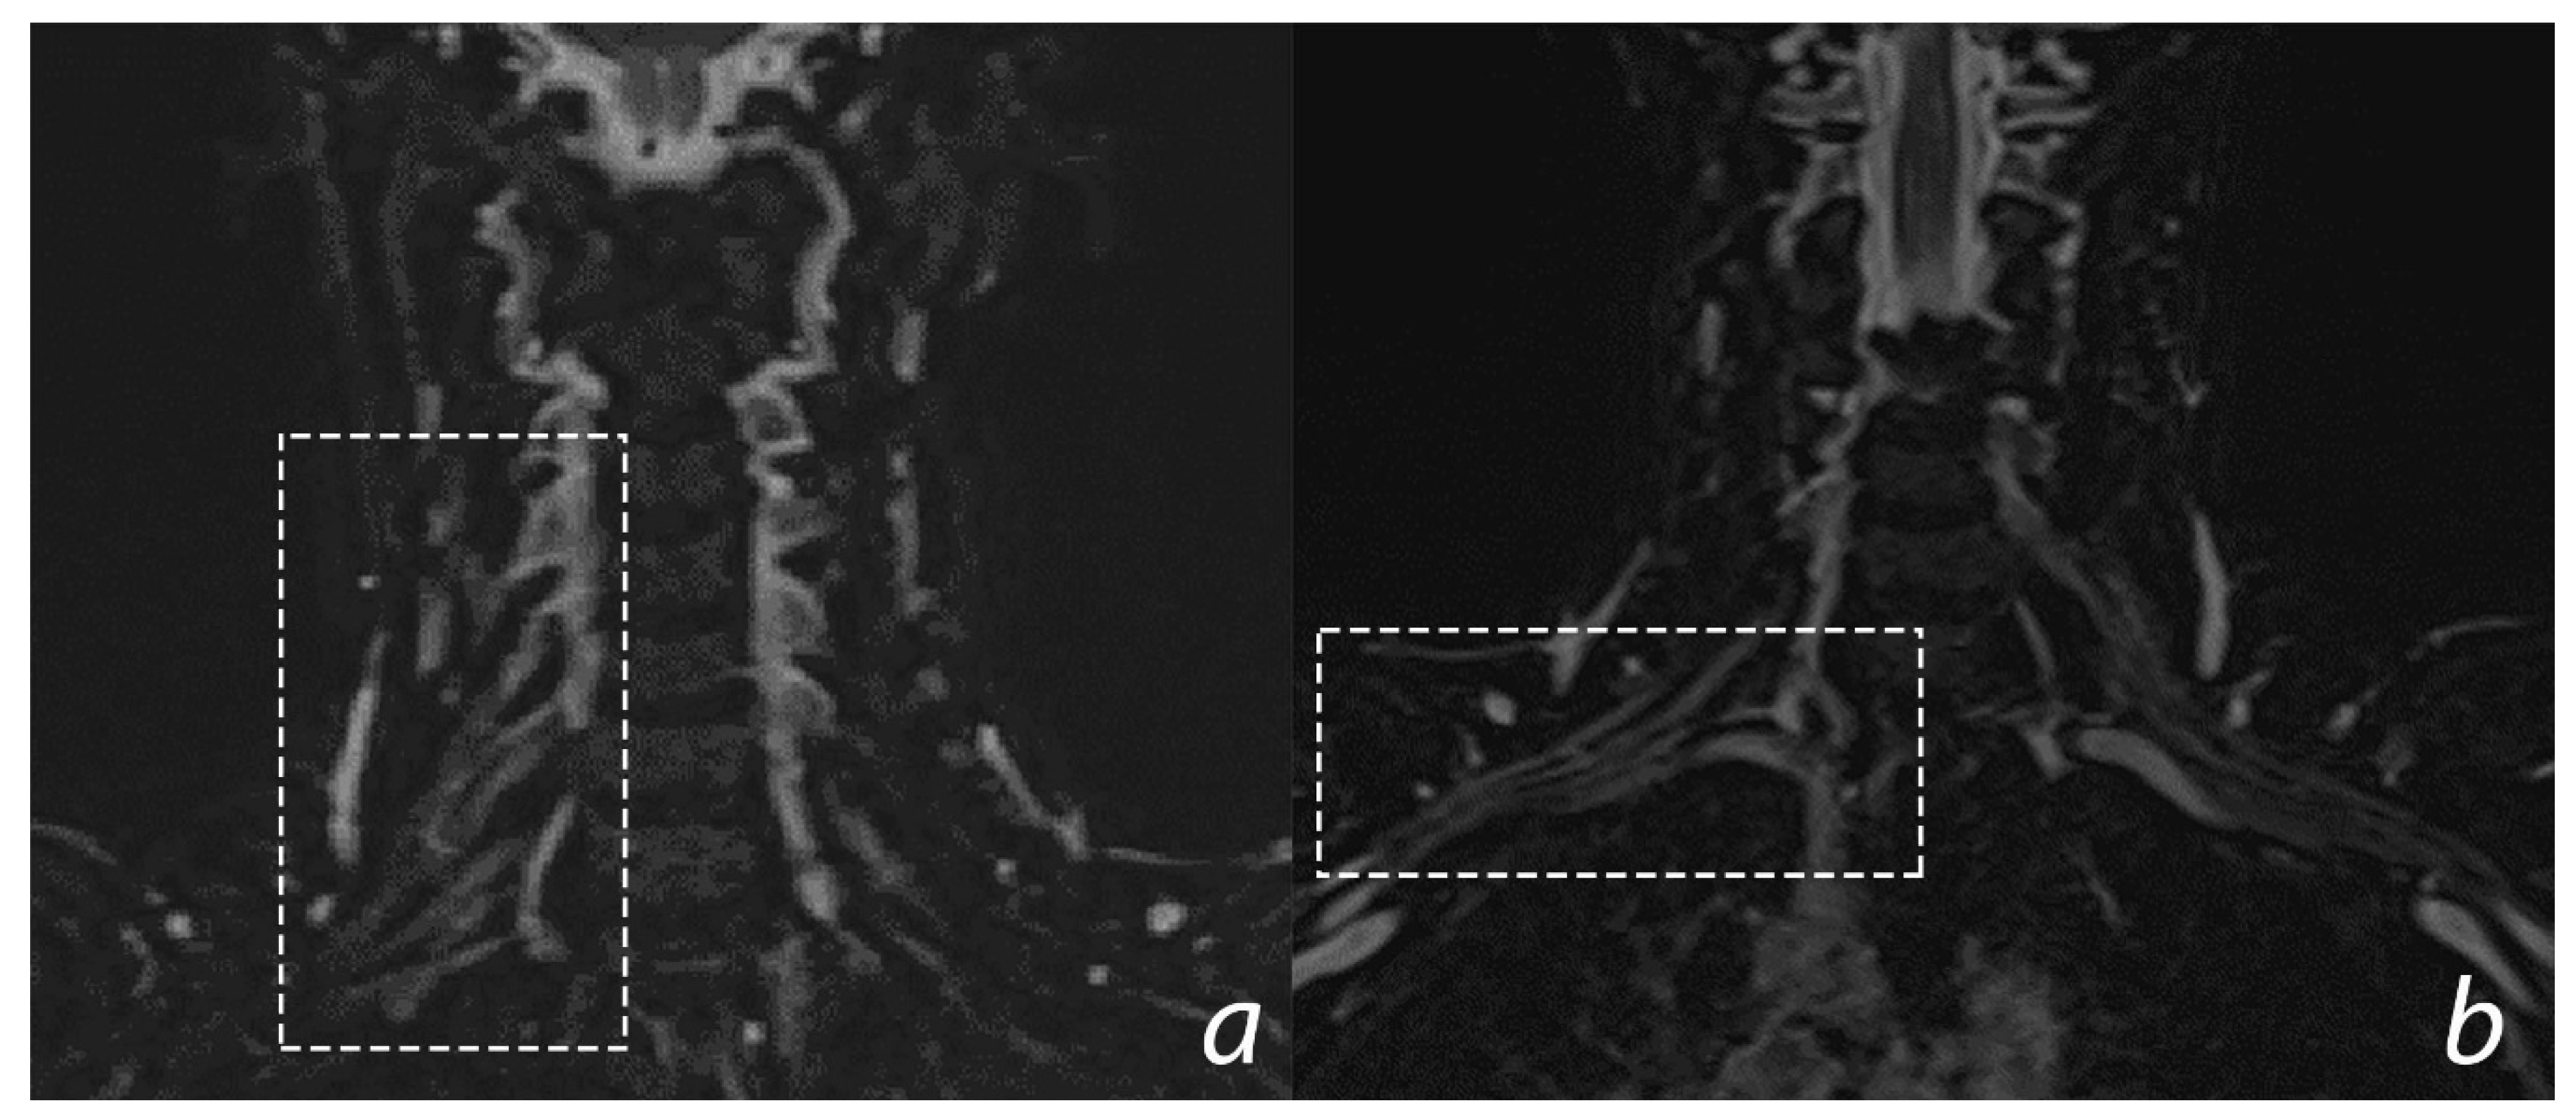

6.3. Imaging

- Gasparotti, R. New techniques in spinal imaging. Neuroradiology. 2011, 53 (Suppl. 1), S195–S197. [Google Scholar] [CrossRef]